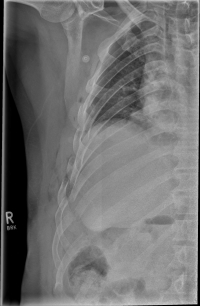

Rippenserie re                   Rippenserie re1

Pneumothorax / tension pneumothorax

In some cases, the sharp rib fragments cause lung or outer chest wall injuries. As a result, air can enter the gap between the lung and chest wall and cause a so-called pneumothorax, which must be treated by drainage.

In rare cases, a so-called tension pneumothorax may develop, which under certain circumstances can also be life-threatening. Due to an injury-related valve mechanism, air from the lungs flows into the gap between the lungs and the chest wall, but can not escape. As a result, the organs are shifted in the chest and concentrated, so that the circulatory function is impaired. It requires, in these cases, an immediate delimbing in the hospital or by an emergency physician.

Rippenserie re1